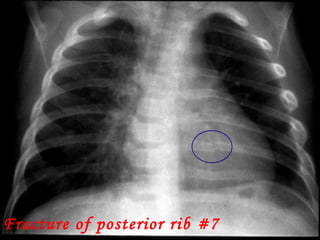

Fracture of posterior rib #7